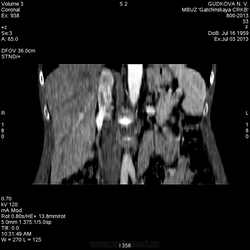

На 3d-реконструкциях выглядит как кавернозная гемангиома, по форме напоминающая желчный пузырь (который я, кстати, не вижу, а УЗИсты описывают) Если это - ж.п., почему так интенсивно копит контраст, и вообще, расположение такое нетипичное?

Еще: кто-нибудь видит желчный пузырь?(УЗИсты описывают и рубцов, после холоцистэктомии, на животе пацинтки не заметил)

Про желчный: нет сканов, где он должен быть в норме. Поэтому сказать, имеется ли он в наличии, нельзя.

И желчный нашел:) Частично сокращенный)